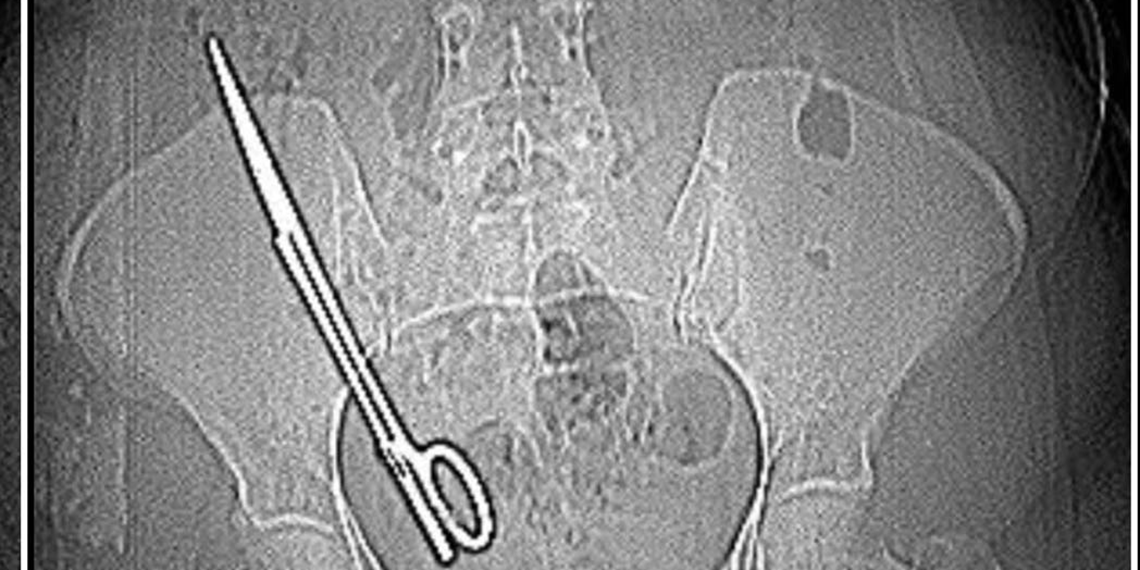

Kala, kendisini ameliyat eden Kadın Hastalıkları ve Doğum Uzmanı Doktor Koray Ş.’ye gidip muayene oldu, röntgen çekildi. İddiaya göre; Koray Ş., 7 yıl önceki ameliyattan dolayı bir komplikasyon oluştuğunu ve acilen ameliyat etmesi gerektiğini söyledi. Doktorun tavırlarından şüphelenen Fatma Kala, ameliyat olmayı reddedip KSÜ Sağlık Uygulama ve Araştırma Hastanesi’ne gitti. Burada yapılan tetkiklerde Kala’nın karnında 16 santimetre uzunluğunda makas olduğu tespit edildi. Ameliyatla karnındaki makas çıkarılıp salığına kavuşan Fatma Kala, hastaneden çıktıktan sonra avukatı aracılığıyla 7 yıl önce ameliyatı gerçekleştiren doktor Koray Ş. hakkında Kahramanmaraş Cumhuriyet Başsavcılığı’na suç duyurusunda bulundu.

Baş ağrısı şikayetiyle gittiği hastanede doktorların ‘Karnında makas var’ deyince şoke olduğunu belirten Fatma Kala, 2017 yılında kist ameliyatı olduktan sonra iç kanama geçirdiğini ve tekrar ameliyata alındığını, makasın da o ameliyatta unutulduğunu söyledi. Karnında makas varken küçük çocuğu ile birçok defa MR odasına girdiğini belirten Kala, “Bundan 7 yıl önce özel bir hastanede ameliyat oldum. O günün gecesinde tekrar iç kanama geçiriyorum ve ikinci ameliyatımı oluyorum. Bu ameliyatta maalesef ameliyat olan bölgemde ameliyat makası unutuyorlar ve biz bunu 7 sonra öğreniyoruz. Baş ağrısından dolayı hastaneye gittik. Hastanede doktorumuz MR’a girmem gerektiğini söyledi.

Ben MR teknisyenine daha önce çocukla beraber MR odasına girdiğimde benim sağ tarafımda çekme olduğunu söyledim. Teknisyen bana ‘Bu şekilde seni MR’a alamam, çok tehlikeli. Acilen ameliyat olduğun doktoru bul’ dedi. Doktorumuz bizi hemen röntgene aldı. Röntgende bir yabancı cisim görmüş ama bize söylemedi, ‘Daha önceki ameliyatından dolayı bir komplikasyon oluşmuş. Seni ameliyat edip dedi o komplikasyonu ortadan kaldırmam gerekiyor’ dedi. Biz doktorun telaşlı tavrından şüphelendik. Eşimle birlikte tıp fakültesine gittik. Oradaki acil doktorlarına başımızdan geçen olayı anlattık. Onlar beni röntgene soktu. Oradan ilaçlı tomografiye girince daha önceki ameliyatımda bırakılan makas orada görüldü. Genel cerrahi bölümünde bu makas çıkarıldı” diye konuştu.